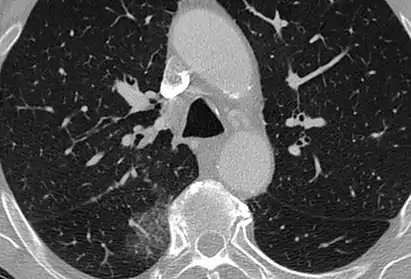

CT image showing patchy areas of ground-glass opacities representing pulmonary edema.